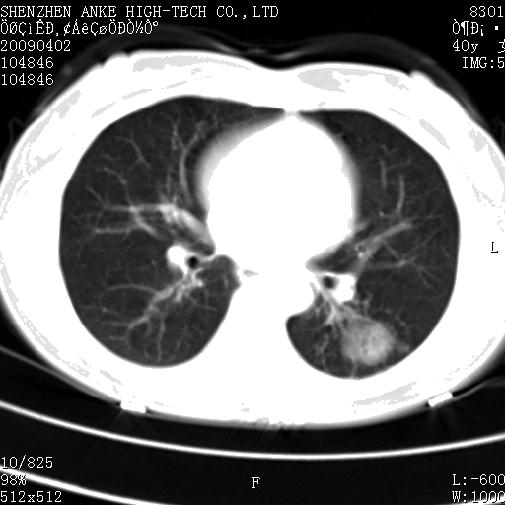

以下是引用随光逐影在2009-4-2 12:16:00的发言:[br]考虑左肺下叶背段继发性肺结核,结核球形成;建议追踪复查。

以下是引用gudu医生在2009-4-2 11:27:00的发言:[br]周围型肺癌

以下是引用卜一在2009-4-2 13:31:00的发言:[br][br] [br] 空洞壁厚不均 胸膜凹陷征。周围型肺癌可能 不排除干酪坏死型肺结核及坏死性肉芽肿。 [br] [br]支持!

以下是引用ct诊断高手在2009-4-2 13:04:00的发言:[br]空洞壁厚不均 胸膜凹陷征。周围型肺癌可能 不排除干酪坏死型肺结核及坏死性肉芽肿。